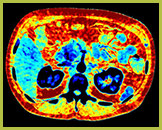

Obraz efektywnej liczby atomowej

Tworzy w oparciu o liczbę atomową tkanki widocznej na obrazie kodowaną kolorem mapę, której można użyć do scharakteryzowania różnych tkanek, np. kamicy nerkowej.